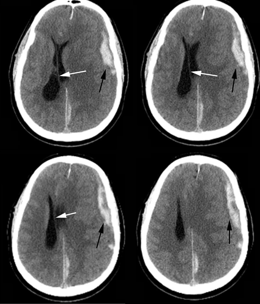

Subdural hematoma

uSeen in 12-29% of TBI

uCollection of blood between dura and arachnoid membrane

uTorn bridging veins

uMay be missed on initial imaging

Can form later

Symptoms often delayed

uMortality rate 40-60%

*If a patient develops sudden lethargy, confusion, headache, dizziness…tell medical team